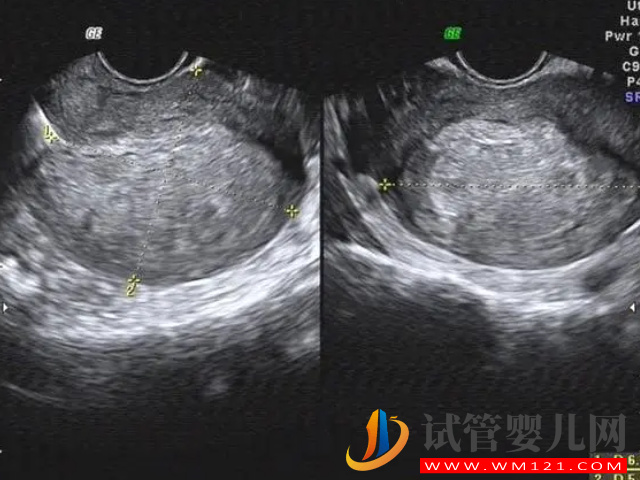

根據(jù)相關(guān)數(shù)據(jù)表明,現(xiàn)目前做試管嬰兒認為的最佳子宮內(nèi)膜厚度為8mm-12mm,對于子宮內(nèi)膜厚度的要求是很嚴格的,因為在移植前都是會檢查的,如果不合格可能就需要先治療,采用凍胚移植,如果不治療就算是移植了,也是會因為子宮內(nèi)膜薄而不著床,或者是正常后出現(xiàn)流產(chǎn)的情況。